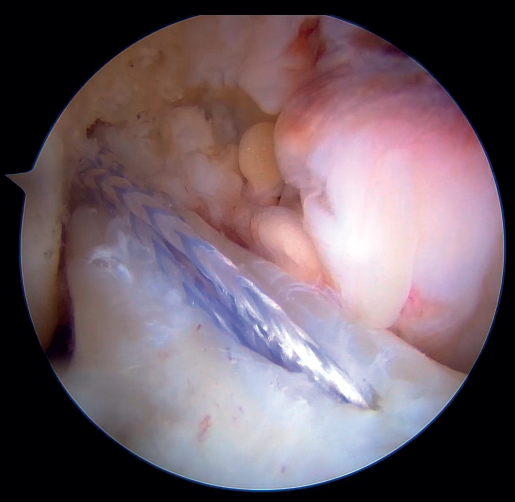

Once a good view of the central compartment is obtained, the area of the femoral footprint of the ACL is prepared to leave exposed bone, and microperforations are made in the medial wall of the lateral condyle to leave a bleeding bed to favor healing of the ligament (Figure 3). These microperforations can be made using specific instruments or with the implant punch. The advantage of using the punch is that the implant insertion site can be prepared at the same time, and only one instrument is used for the entire process (Figure 4). This step can be done after the suture has been prepared in the ligament, although doing it beforehand avoids the threads from standing in the way. The ideal point for fixation is just anterior to the native ACL footprint, although if the tear is partial or corresponds to Sherman I, it can be taken to the anatomical footprint without difficulty.

The anteromedial and posterolateral fascicles of the ACL are then identified for suturing separately. Using a suture passer, a closed loop suture is passed through the anteromedial fascicle at its most distal zone, and the loopless extremity is carried alternately (medial to lateral, lateral to medial and so on) to the most proximal zone, usually involving 3 or 4 passes of the suture. The thread may knot on itself during suturing if we are not attentive to it on entry and exit. To solve this problem, we simply undo the knot with retrieval forceps and repeat the step if necessary.